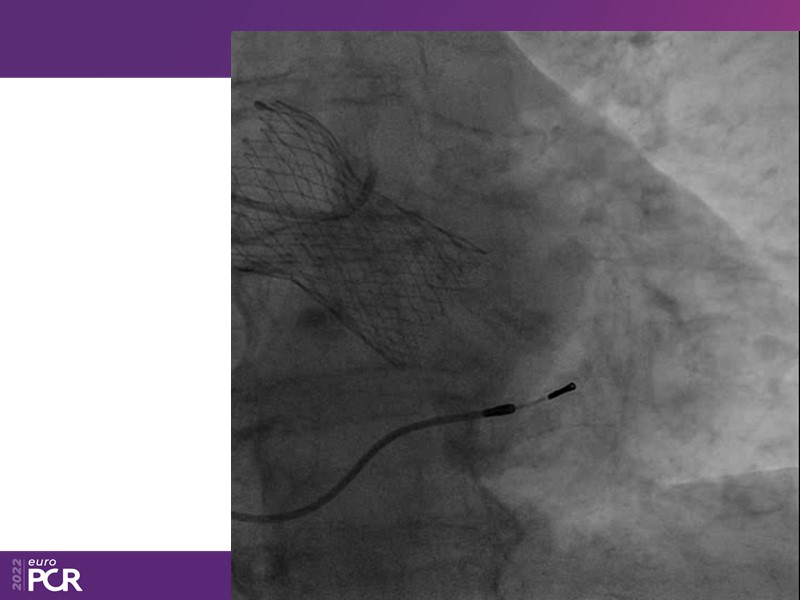

Consult this session to learn how to contribute to streamlined pre- and post-TAVI patient pathways, to discover updates on the optimised TAVI procedure and appreciate the variances in different valve designs and the long-term patient outcomes, as well as to discuss the right time of PCI in TAVI patients (steps on the procedure).